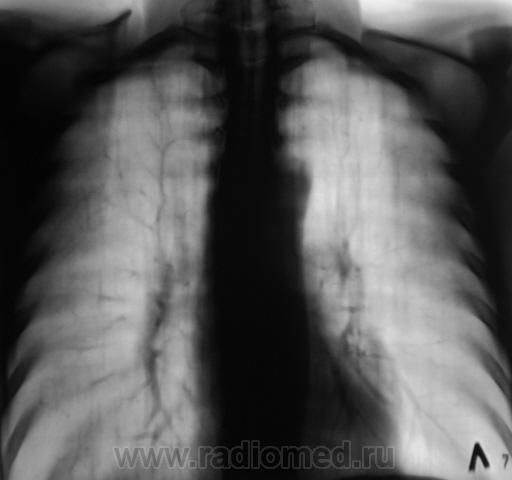

Рентгенограмма.

С двух сторон в верхних долях очаги. На вскидку tbs. А что с клиникой, анализами, анамнез.

Двусторонний очаговый туберкулез.

В s 1 -2 и глубоких отделах s6судя по срезам очаги,справа с включениями кальция,на фоне фоброзно измененного легочного рисунка

Скорее диссеминирмванный так как пораженно более 2-х сегментов.